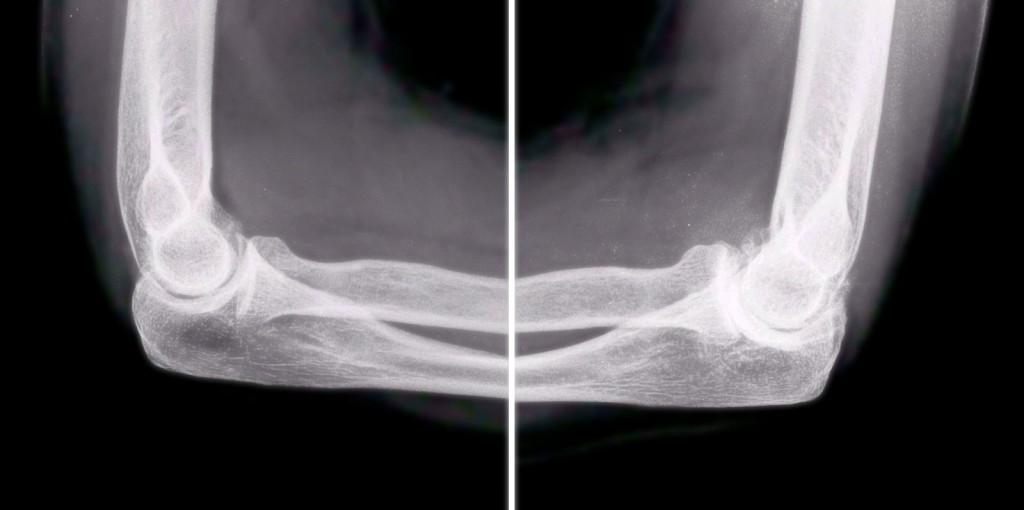

Оссификаты Локтевого Сустава: Диагностика и Лечение

Раздел: Секреты мастерства